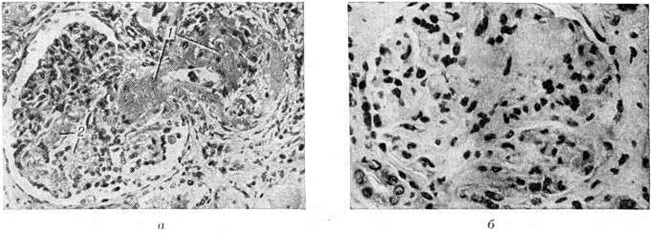

Рис. 3.

Микропрепараты почки при злокачественной форме нефросклероза: а — в центре виден почечный клубочек с фибриноидным некрозом приводящего сосуда (1) и клубочковых кровеносных капилляров (2); окраска гематоксилин-эозином; × 310; б — почечный клубочек с резким склерозом петель кровеносных капилляров и уменьшением числа эндотелиоцитов; окраска гематоксилин-эозином; × 525.